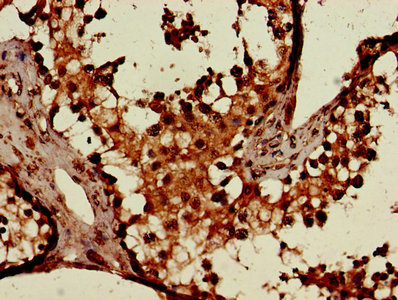

Immunohistochemistry of paraffin-embedded human testis tissue using CSB-PA006046LA01HU at dilution of 1:100

CSB-PA006046LA01HU